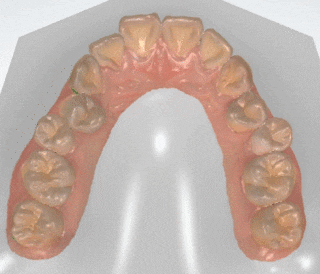

첨단 3D 스태너를 이용한 교정 심뮬레이션

3D 시뮬레이션을 통한 교정결과 예측